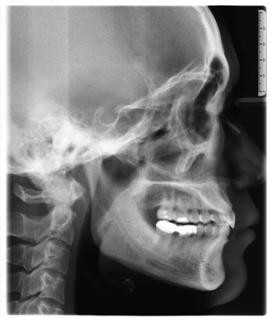

臨床診斷:通過3D數(shù)字化全景機(jī)的檢查,患者的上牙前突屬于牙性,非骨性問題,雙唇閉合時(shí)可見明顯隆起,X片顯示根尖無異常,上下后牙存在間隙,可通過美國MBT直弓絲正畸技術(shù)將其矯正復(fù)位,收攏間隙,矯正所需時(shí)間一年半左右。

全景機(jī)側(cè)位片